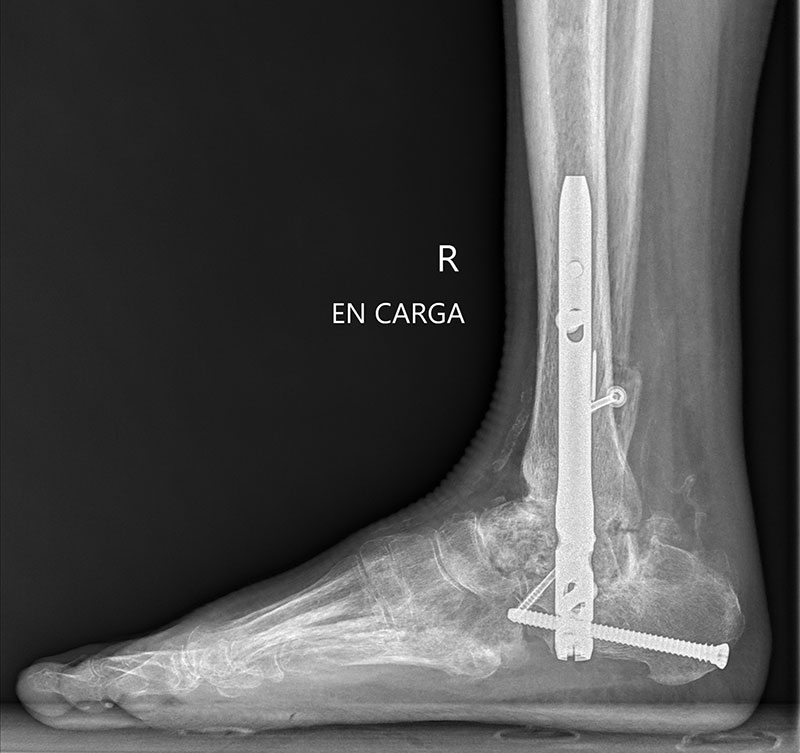

Después